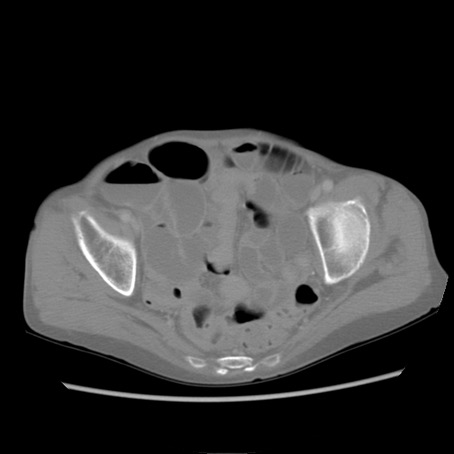

症例25(横断像)

【症例】80歳代女性

【主訴】胸のつかえ感

【現病歴】約9時間前に食後から胸のつかえた感じあり、嘔吐あり、来院。

【既往歴】胃癌(全摘)、胆摘、虫垂炎

【身体所見】心窩部に圧痛あり、反跳痛なし。

【データ】WBC 5700、CRP 0.05